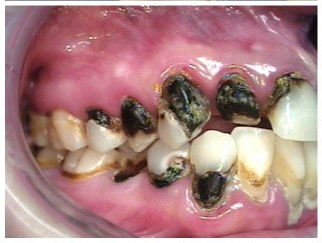

Often, the most visually striking manifestation of long-term meth use—known as “meth mouth”—is caused by the lack of saliva combined with an increase in soda drinking and extremely poor oral hygiene. This typically leads to meth abusers experiencing a large amount of caries. Decay begins with occlusal and facial caries and progresses rapidly, decaying to the bone level and often leaving only roots (Figure 1 through Figure 3).16

Fig 3. After 5 years of meth use in a 22-year-old male patient, cervical decay and coronal fractures were evident.

Figure 3